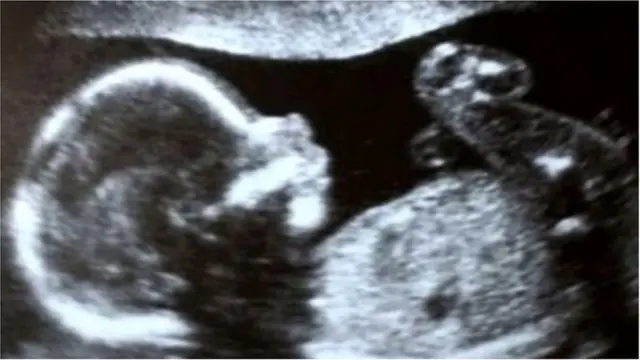

17 నెలలుగా గెలాక్సీలో చికిత్స పొందుతున్న మీనాక్షి వలాండ్ అక్టోబర్ 18న సిజేరియన్ అనంతరం ఒక పాపకు జన్మనిచ్చారు. పుట్టిన కొద్ది సేపటికే ఆ పాప దేశవ్యాప్తంగా సెలిబ్రిటీ అయిపోయింది.

దీనికి కారణం ఆ పాప కేవలం భారతదేశంలోనే కాకుండా, ఆసియా-పసిఫిక్ ప్రాంతంలోనే మొట్టమొదటిసారి గర్భాశయ మార్పిడి ద్వారా జన్మించింది.

మీనాక్షి గర్భాశయంలో రాధ 32 వారాలు ఉంది. పుట్టినపుడు ఆ పాప బరువు 1 కిలో 450 గ్రాములు.